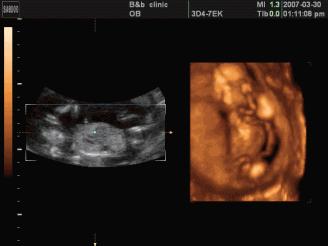

是立体动态显示的彩色多普勒超声诊断仪,可以进行胎儿头面部立体成像,可显示眼、鼻、口、下颌等状态,协助医生直接对胎儿先天畸形进行诊断,价格比普通彩超价格贵。

●四维彩超

四维彩超能够对胎儿进行动态、立体超声检查,显示胎儿的面部、各器官的发育情况,甚至胎儿在母体里的状态也可以观察到;对胎儿畸形,如唇裂、腭裂、骨骼发育异常等能早期诊断。另外还能制作成光盘,让宝宝拥有最完整的0岁相册,留下永久的记忆。